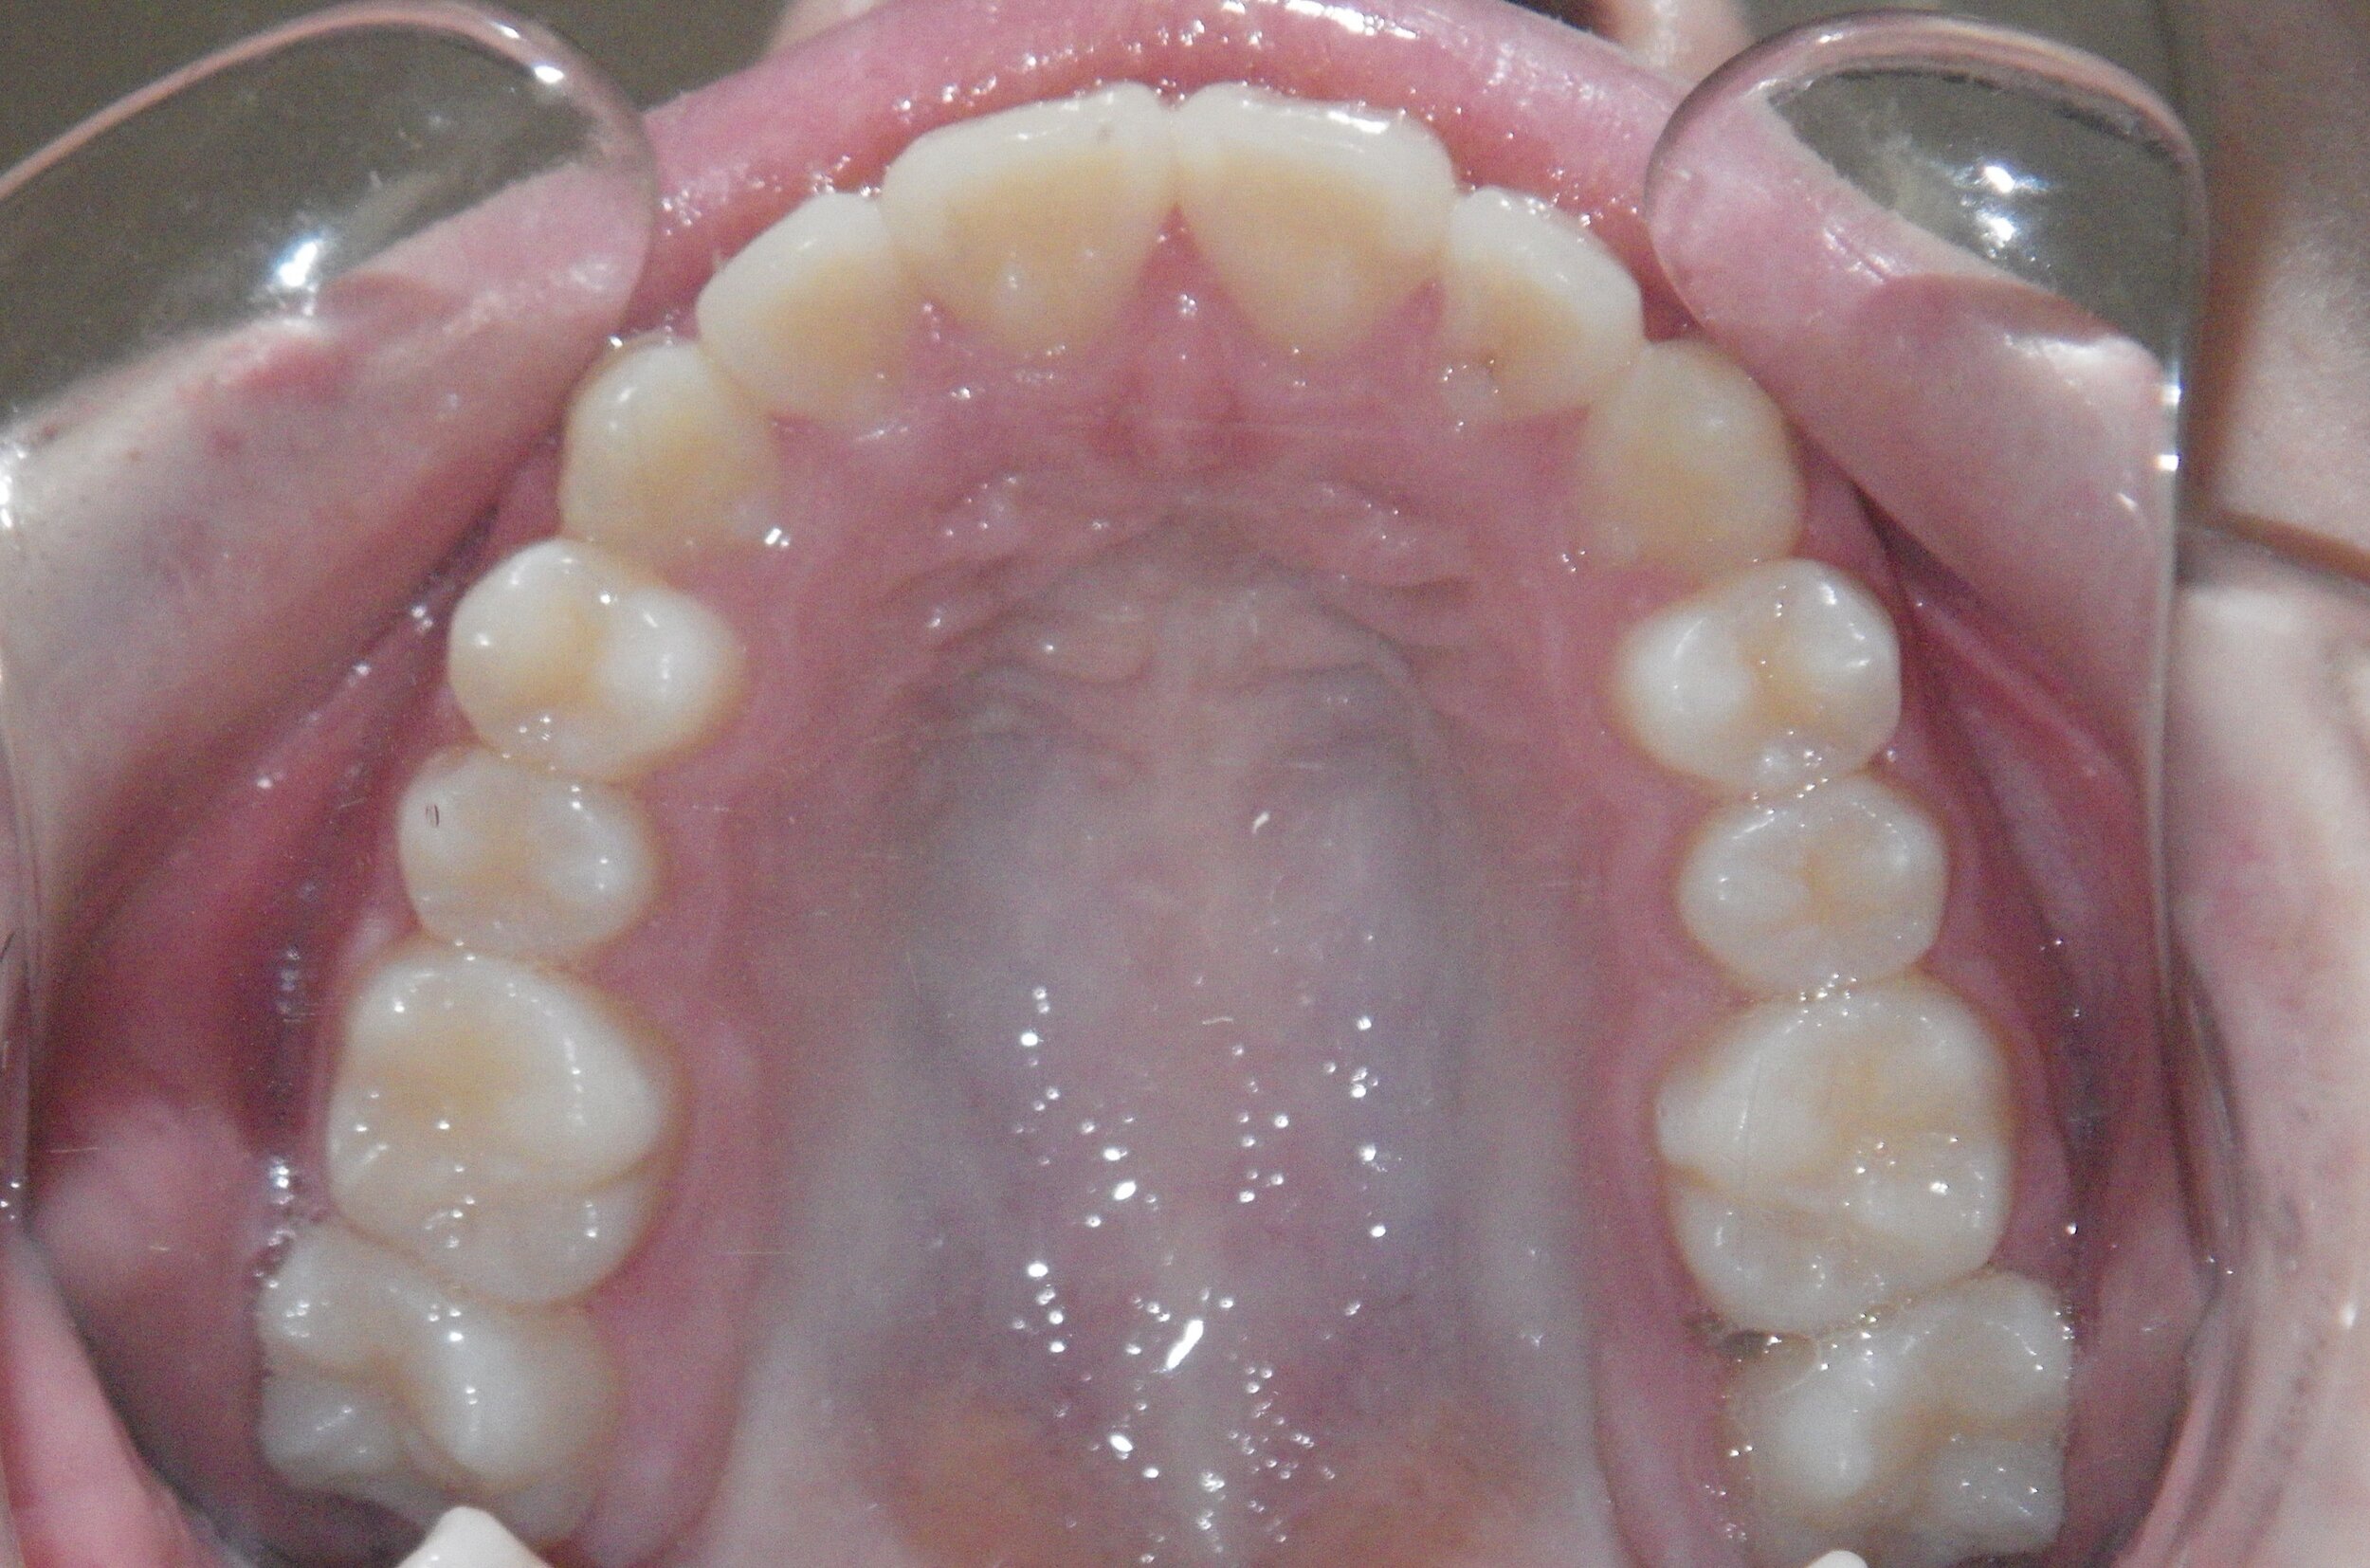

Phase I can be used to help change unfavorable growth or to make room so all the adult teeth have room to erupt. Here, we used Phase I to make room for the adult canines and followed up with Phase II treatment to a get a great esthetic and functional result!